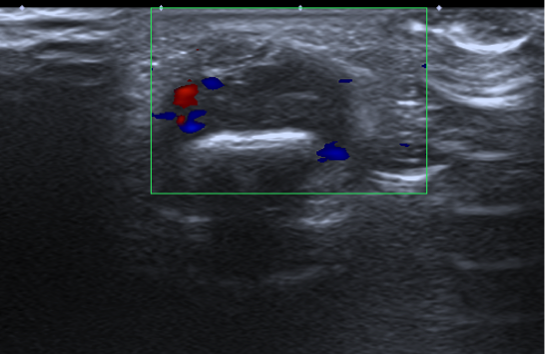

Mujer de 24 años, sin antecedentes de interés, que presenta tumoración en el 2º dedo de la mano derecha. Nota crecimiento progresivo.

No dolorosa, aunque limita algo la movilidad activa. La movilidad pasiva es completa.

Se solicitan pruebas de imagen: RX, ECO, RM.

1. ¿Como describirías los hallazgos en RX y ecografía?

- A. Tumoración de partes blandas que asocia erosión ósea adyacente.

- B. Tumoración de partes blandas sin erosión ósea adyacente.